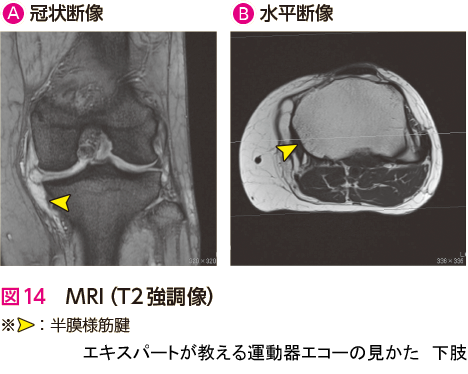

症例 6大腿骨内顆骨壊死(脆弱性骨折)